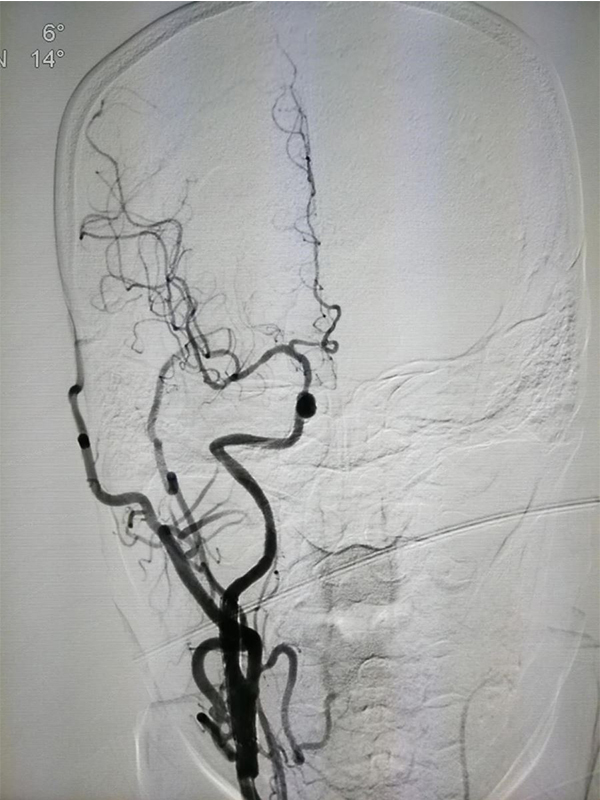

MRA CTA (CT ) DSA <50 %) MRA 50 % CTA 80% DSA 99 % ( ) CTA DSA

MRA ( 3D-TOF) MRA MRA MRA

MRA CTA MRA ( ) MRA